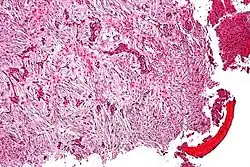

| Micrograph (using H&E stain) of an adamantinoma showing the biphasic histomorphology. | |

Adamantinoma (from Greek adamantinos 'very hard'[1]) is a rare bone cancer, making up less than 1% of all bone cancers.[2] It almost always occurs in the bones of the lower leg[3] and involves both epithelial and osteofibrous tissue.[4]

Histologically, islands of epithelial cells are found in a fibrous stroma. The tumor is typically well-demarcated, osteolytic and eccentric, with cystic zones resembling soap bubbles.[2]